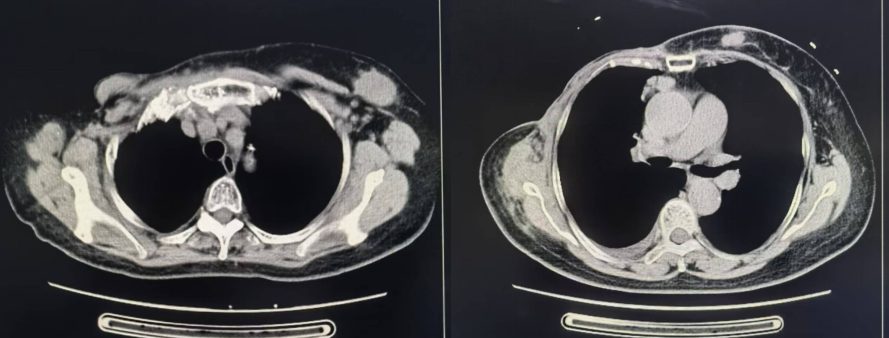

胸部CT(2024年05月22日 我院):

图 胸部CT(2024年05月22日 我院)

1、右侧乳腺术后改变,术区周围皮肤增厚,考虑复发可能,请结合临床。

2、右侧胸背部肌肉肿胀,肌间隙及皮下多发结节影,右前上纵隔及左侧腋窝多发增大淋巴结影,最大约3.6*2.7cm,左前胸壁皮下多发结节影,最大约1.6*1.1cm。

3、右侧胸膜多发结节状增厚,右侧少量胸水,右肺下叶实性小结节影,考虑转移。